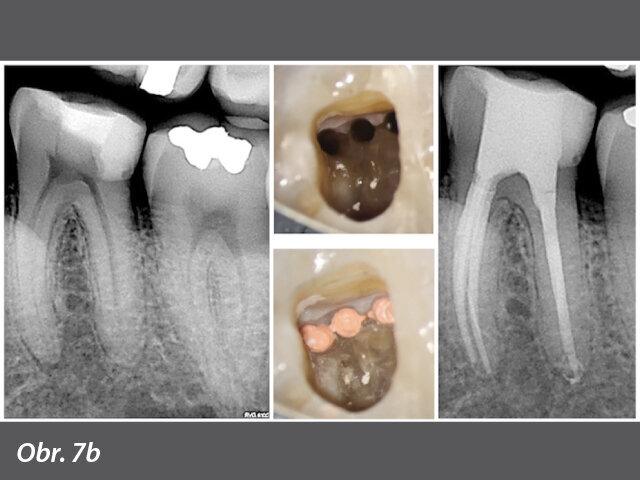

Nová generace nástrojů s adaptivním/virtuálním jádrem, systém XP-endo (FKG Dentaire, Švýcarsko), dramaticky změnila pohled na endodontické nástrojové vybavení. Při nepřítomnosti pevného jádra reflektuje tento systém zubem danou dosažitelnou konfiguraci kanálku a umožňuje čištění s takovým stupněm důkladnosti, který je naprosto bezprecedentní. Obrázek 7 podrobně popisuje různé vlastnosti XP-endo Shaper. Vodicí špička hrotu se vejde do předem vyhotovené skluzné dráhy (glide path), která zajišťuje přesné vedení a vycentrování nástroje. Tradiční nástroj pro vytvoření glide path se používá v souladu s nástrojem # 15/0,02 (velikost/kónicita). Na hrotu vodicí špičky nástroje nejsou žádné řezné břity a nástroj XP-endo Shaper zajíždí do vypreparované apikální komponenty glide path do hloubky 0,25 mm. Další část 0,25 mm vodicí špičky je nakonfigurována pomocí šesti řezných břitů. Rotace těchto břitů rozšiřuje dalších 0,25 mm prostoru kanálku kdekoli od nástroje # 25/0,02 až po # 60/0,02; nicméně apikální velikost zvolená pro XP-endo Shaper je # 30. Zúžení XP-endo Shaper je 0,01; avšak slitina MaxWire Shaperu umožňuje martenzitickému tvaru při pokojové teplotě zapamatovat si tvar, jak je ilustrováno při tělesné teplotě (obr. 6). Opakovaným pohybem nástroje v jednom směru (pohybem analogickým s řezáním na rozdíl od krátkého dotknutí špičkou nástroje) se vytvořený kónus pohybuje v rozsahu od 0,02 do 0,08. Ideální zúžení uvnitř kanálku v celé jeho délce je 0,04, což zachovává dentinový obvod v koronální třetině a maximálně zachovává dentin v každé oblasti zakřivení kořene. Obrázek 7a ukazuje rozdíl mezi schopností standardního kulatého NiTi nástroje vyčistit méně než ideální objem zbytků nečistot uvnitř kanálku, na rozdíl od výraznějšího maximálního debridementu dosaženého adaptivním diskontinuálním kontaktem stěn kanálku s XP-endo Shaperem. Požadovaný minimálně invazivní tvar kanálku dosažený tímto jedinečným nástrojem je znázorněn na obrázku 7b.